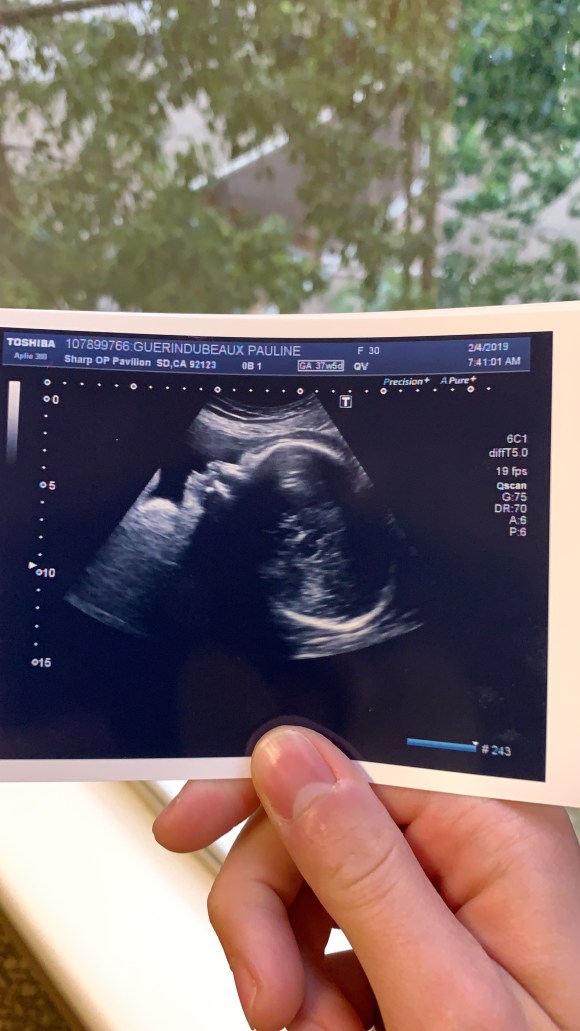

Lundi matin, nous avons fait la dernière échographie (la quatrième) de notre petit bébé à venir.

Et nous avons alors appris que notre bébé était imposant (pour rester poli) ! 3,7 kilogrammes selon leurs prédictions. Mais il pourrait largement être à 4 d’après la personne qui nous a fait l’écho…